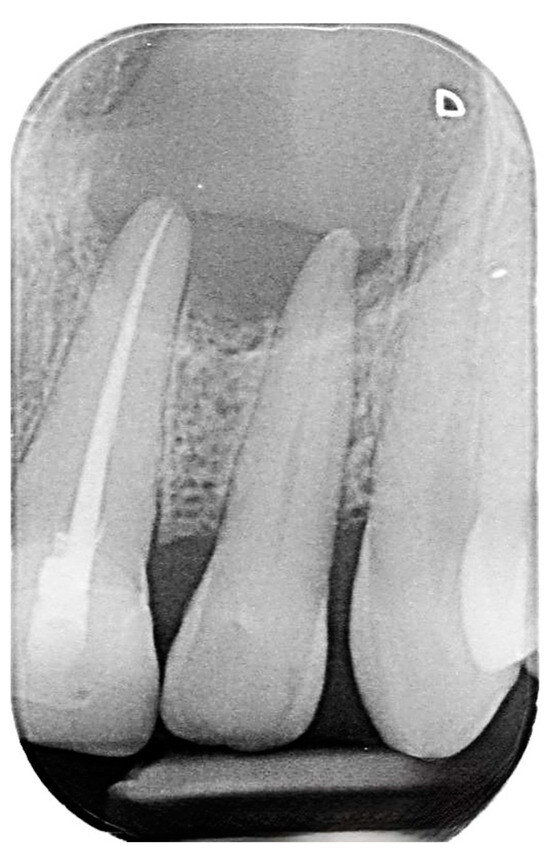

2.2. Delivery of Treatment

2.4. Healing of the Defect and Follow Up